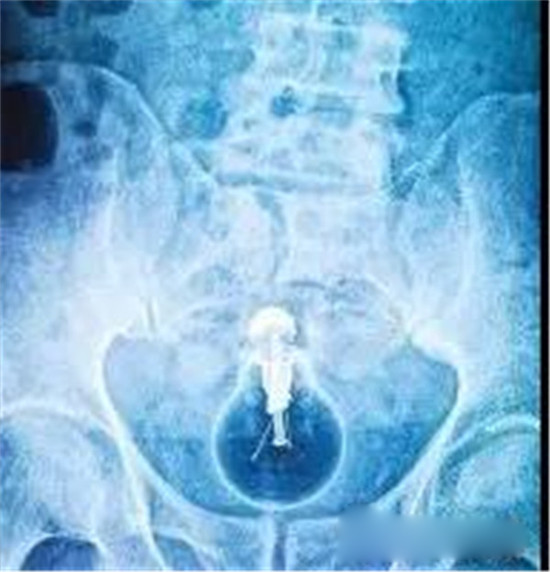

下面我们来看看常见的这些直肠异物。为了保护病人的隐私,X光片已经经过技术处理,看不出任何病人的信息。

这是一个啤酒瓶。男性。

上面是一个啤酒瓶在大肠里。病人是男性。这是常见的肛门内异物。

这种情况,往往只要给病人打上全身麻醉,肛门松弛后,就可以用卵圆钳经过肛门把啤酒瓶拉出来。